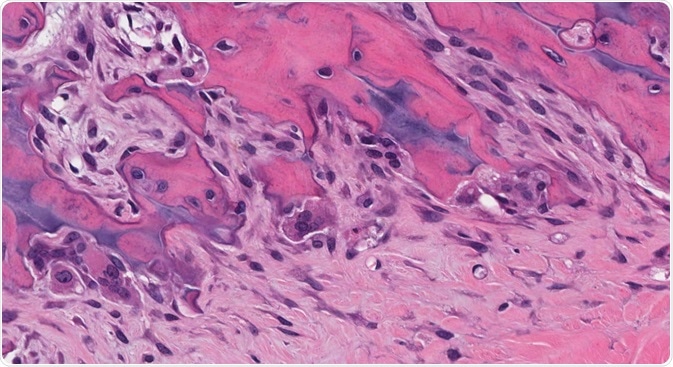

Credit: vetpathologist/Shutterstock.com

Osteoclasts are large multinucleated cells with a myeloid lineage, which have the function of clearing away mineralized and calcified constituents of the bone matrix which are aged or damaged. They have 2-12 nuclei (typically 5) and are 150-200µm in diameter. They are strongly acid-phosphatase-positive.

There are two distinct features of an osteoclast: a ruffled border and a sealing zone. The ruffled border is composed of a convoluted membrane that develops by the merging of secretory lysosomes with the plasma membrane. The sealing zone contains an actin filament ring which surrounds the ruffled border, isolating the acidified microenvironment inside the cell from the general extracellular space.